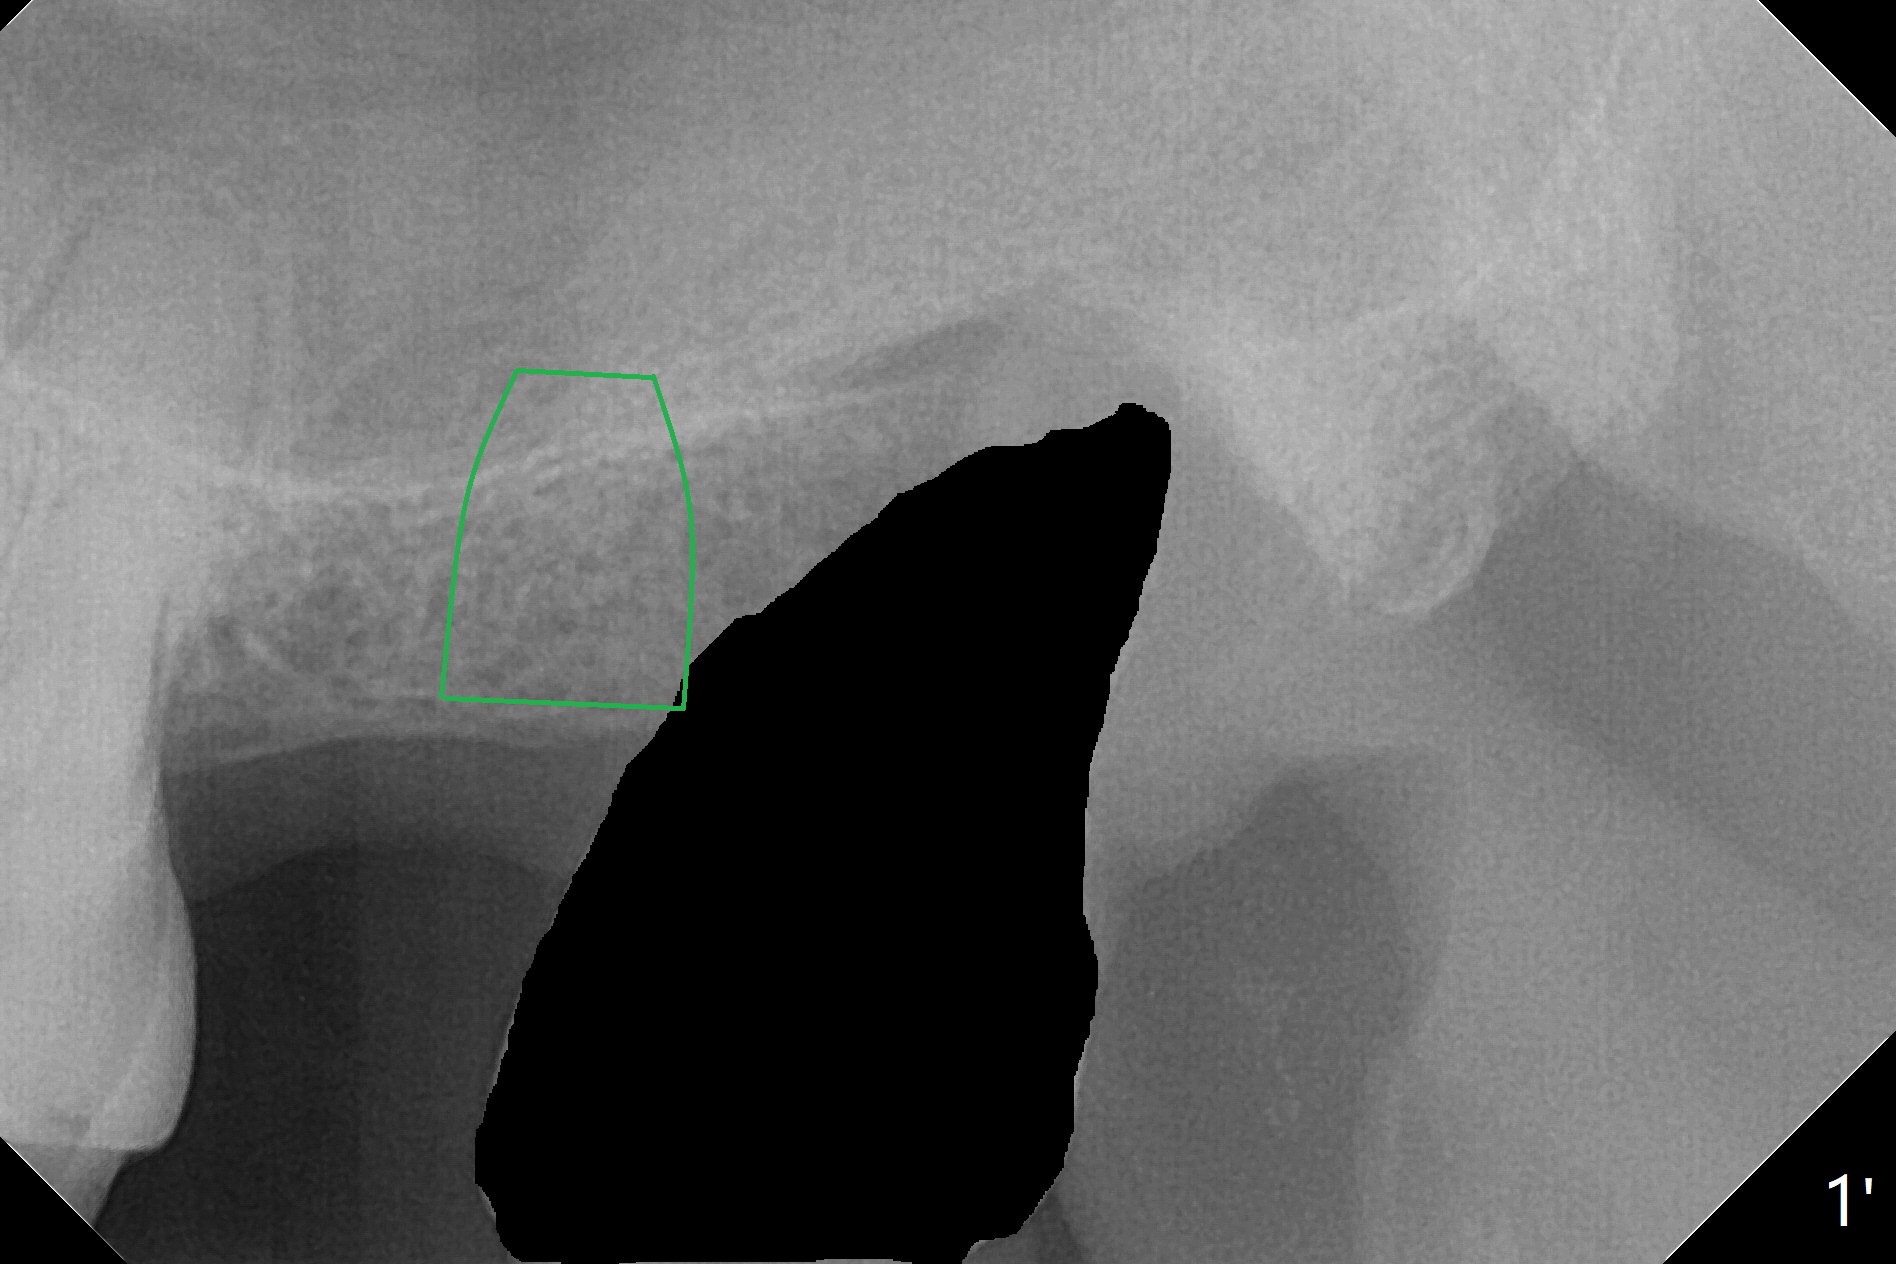

68岁男,缺失15号牙,由单颗牙局部托牙修复。当16号牙松动,近中移位,病人考虑拔除16号牙,经过讨论他同意在15号牙种植,治疗计划(图一)?17,18号牙存在。最佳方案:16号牙拔除(图一’:黑色),同期15号牙种植(绿色)。不过病人马上要出差,只好先拔牙(第二方案),需要植骨(图一”:圆圈)?其实需要植骨(图二:*),因为16号牙牙槽窝(图三:红虚线)侵犯15号牙植牙区(绿色)。植骨减少后期种植,植体螺纹远中螺纹暴露。